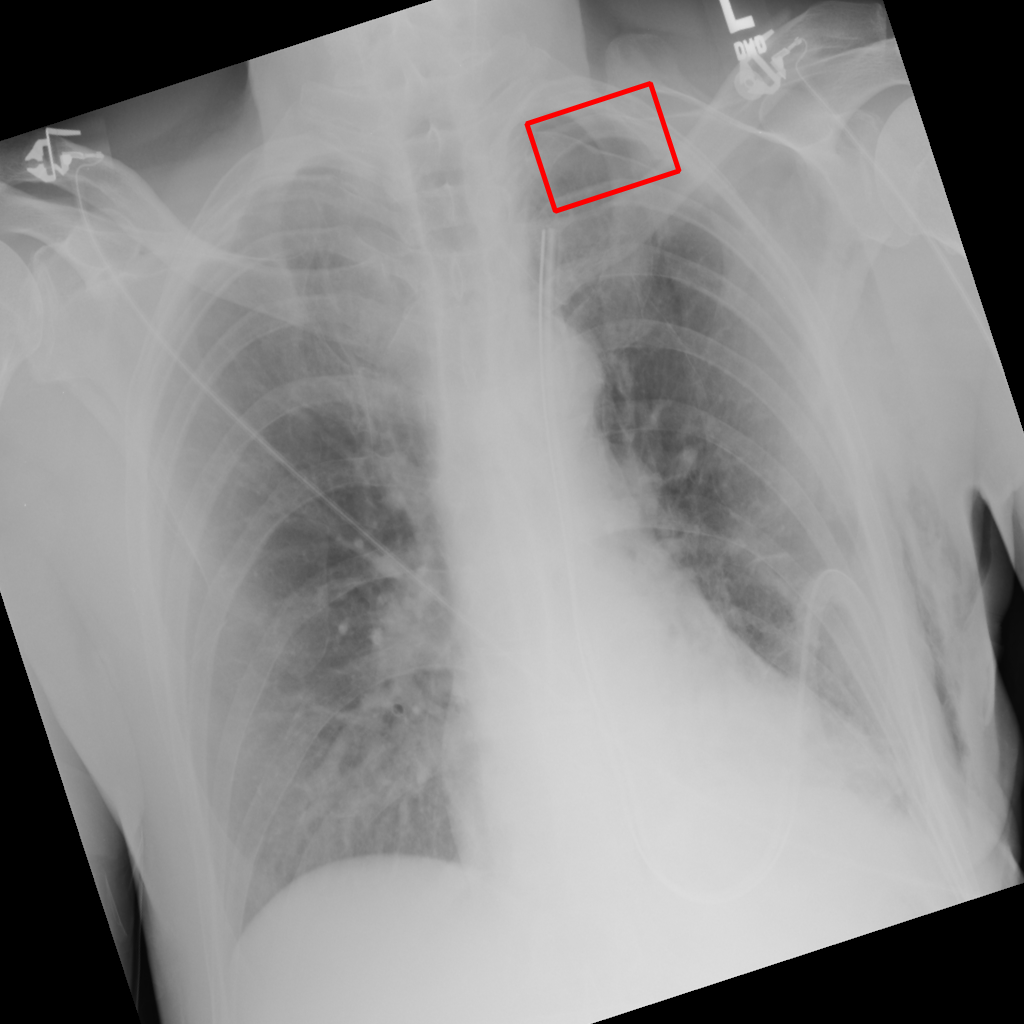

Object Rotation

X-ray GMAIMMbench Disease Diagnosis

Object Rotation - L2 (Severe)

L2

L2 (Severe)

Question

Given the boxed region in the X-ray image, which abnormality is the image most indicative of?

A pneumothorax B pulmonary fibrosis C bone fracture D pleural effusion

Ground Truth: A. pneumothorax